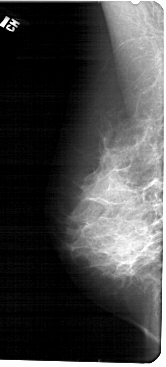

A_1682_1.LEFT_MLO

LEFT_MLO LINES 5491 PIXELS_PER_LINE 2476 BITS_PER_PIXEL 12 RESOLUTION 43.5 NON_OVERLAY